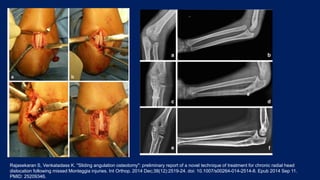

They did z shaped sagittal osteotomy, distracted, angulated and fixed

with one medio-lateral screw

Post op immobilised in AE slab for 6 weeks followed by gradual

mobilization

Rajasekaran S, Venkatadass K. "Sliding angulation osteotomy": preliminary report of a novel technique of treatment for chronic radial head

dislocation following missed Monteggia injuries. Int Orthop. 2014 Dec;38(12):2519-24. doi: 10.1007/s00264-014-2514-8. Epub 2014 Sep 11.

PMID: 25209346.